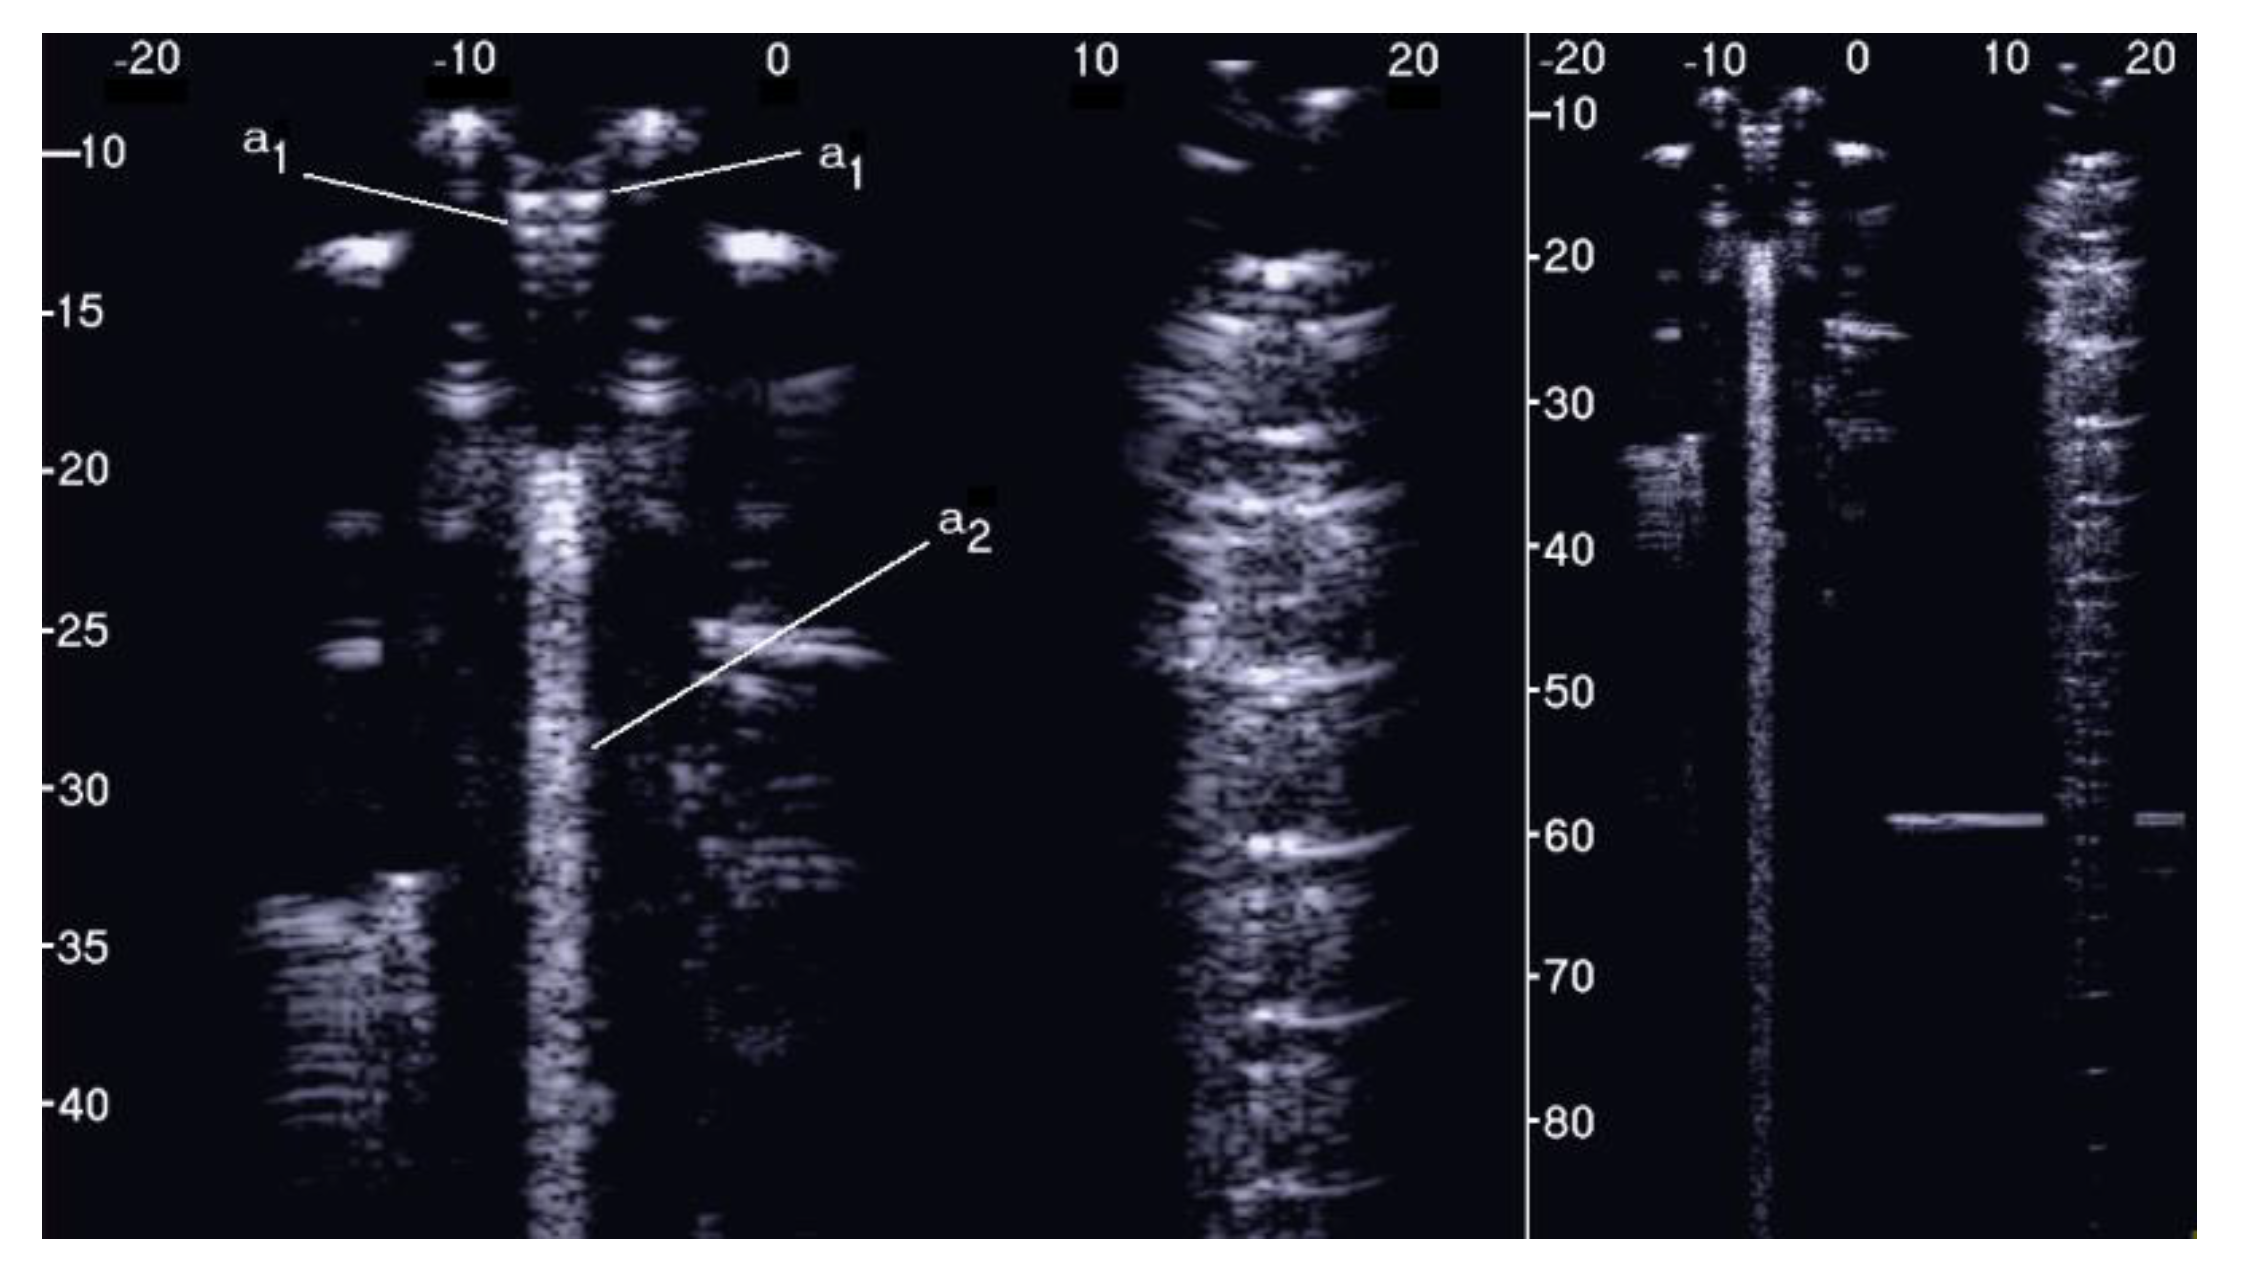

The simulated septa, which were obtained by using the pair of external moulds printed by setting the spatial resolution of the 3D printer to 0.1 mm, were first analysed. The first four images in Figure 10 from left to right show the artifacts which were obtained on four different simulated septa with smooth lateral surfaces and with thicknesses equal to 1.2, 0.8, 0.6, and 0.4 mm. It is worth noting that in this case, the vertical artifacts begin just below the upper polyethylene film. The septa with a thickness equal to 0.8, 0.6, and 0.4 mm provided modulated artifacts even though the 0.8 mm septum showed a slightly confused modulation. However, Figure 10 also shows an unexpected acoustic sign which is not observed on US lung images. The whiter sign, which is observed within the modulation of the three artifacts, is given by the reflection of the lower polyethylene film. The bottom of the septa gives rise to a reflection which is clearly highlighted in Figure 10, and this experimental result is not consistent with the observations of the physicians. Therefore, the simulated septa, which were obtained by using the pair of external moulds printed by setting the spatial resolution of the 3D printer to 0.280 mm, were also analysed. The vertical artifact which was obtained on a 0.4 mm septum with rough lateral surfaces is shown in the last image on the right of Figure 10. The strong reflection of the bottom of the septum is still perceivable, but this time, it is partially masked within the vertical artifact, and the latter is closer to the artifacts which are observed on US pulmonary images. Modulated vertical artifacts were obtained, and a correlation with the thickness of the septa emerges again, as expected by physicians.

Figure 10. From left to right: the first four images show the vertical artifacts which were obtained with agar septa having smoother lateral surfaces and thickness equal to 1.2, 0.8, 0.6, and 0.4 mm. The last image on the right shows the vertical artifact which was obtained with an agar septum with rough lateral surfaces and a thickness equal to 0.4 mm. The two thick white lines at the top and at the bottom of every image represent the reflection of the upper polyethylene film and its replica, respectively. The arrows indicate the reflection of the lower polyethylene film.